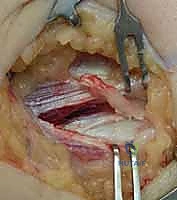

1. الجراحة المفتوحة الدقيقة (Open Debridement - Nirschl Technique)

هي المعيار الذهبي التقليدي، ولكن الدكتور هطيف يجريها بتقنيات الجراحة المجهرية الحديثة (Mini-open) من خلال شق جراحي صغير جداً لا يتجاوز بضعة سنتيمترات.

خطوات العملية المفتوحة:

* يتم إجراء شق جراحي صغير فوق اللقيمة الوحشية.

* يتم إزاحة العضلة الباسطة للأصابع (EDC) برفق للوصول إلى الوتر المتضرر (ECRB).

* يتم استئصال النسيج الندبي والتنكسي الرمادي اللون بدقة متناهية (Excision of angiofibroblastic tissue).

* تقشير العظم (Decortication): يقوم الدكتور هطيف بعمل ثقوب دقيقة جداً في عظم اللقيمة الوحشية. هذا الإجراء الحيوي يسمح بخروج الخلايا الجذعية وعوامل النمو من نخاع العظم إلى منطقة الوتر، مما يحفز بناء نسيج وتري جديد وقوي.

* يتم إعادة خياطة الأنسجة السليمة بخيوط جراحية متينة، ثم إغلاق الجرح تجميلياً.